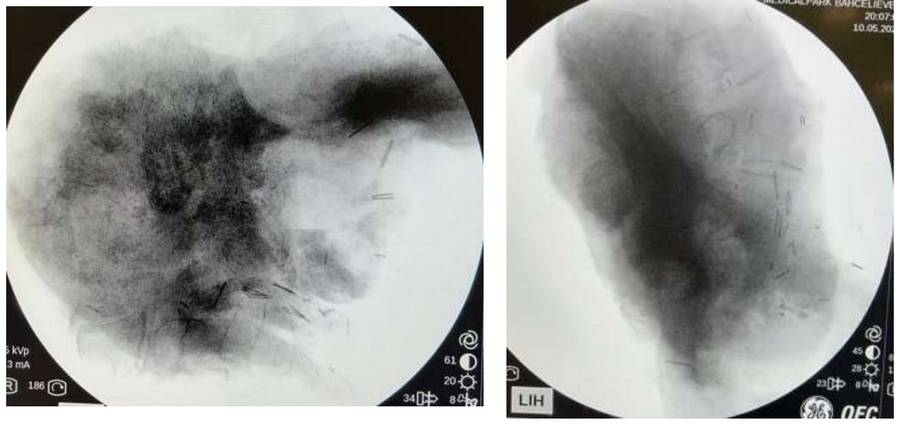

During the operation: Fluoroscopy image of the removed tumor tissue.